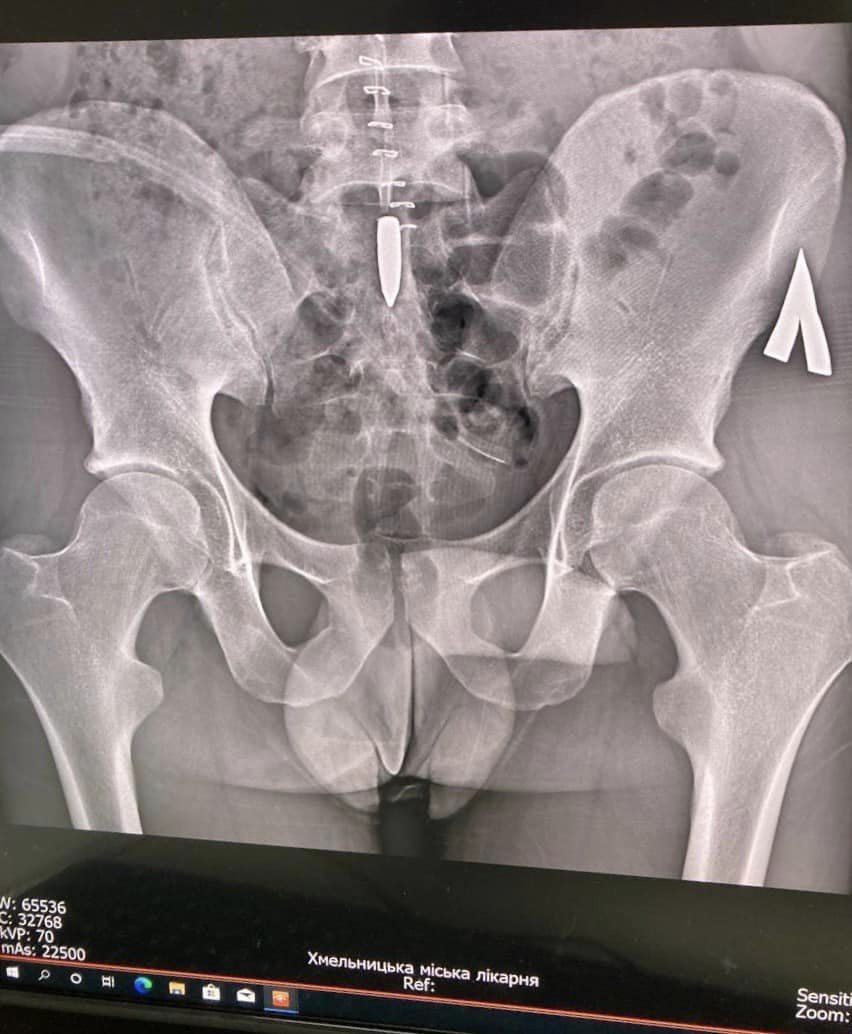

Медики зазначають, що під час бойових дій захисник отримав вогнепальне поранення. Куля калібром 7.42 пройшла через живіт та опинилась у попереково-крижовому відділі хребта. Вона пробила тверду мозкову оболонку, поміняла траєкторію вниз, і застрягла у попереку, між сакральними нервовими закінченнями, які відповідають за рухи тазу та нижніх кінцівок.